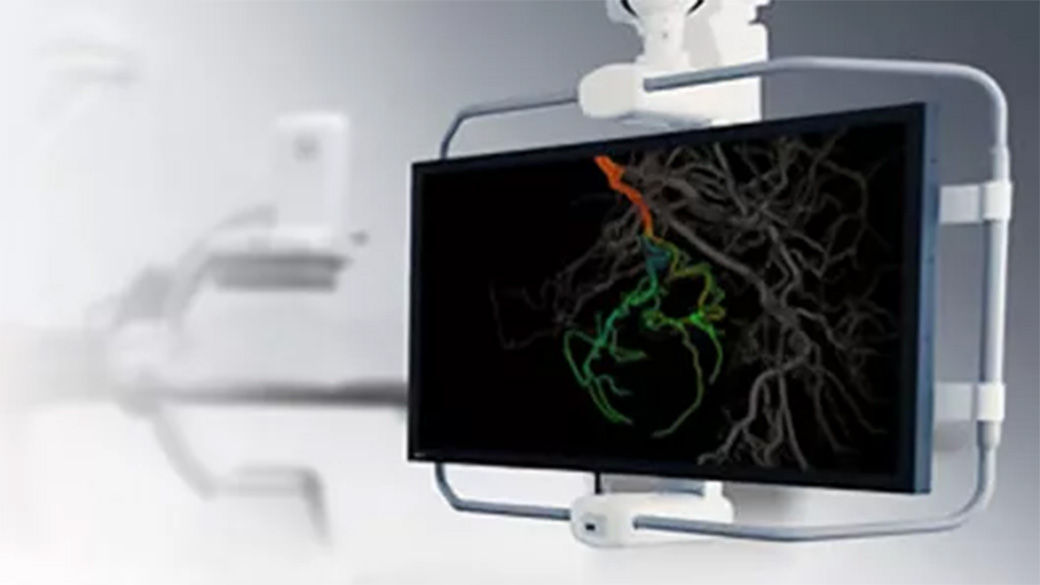

Advanced 3D roadmap

Augmented image capabilities for catheter guidance

Select from the sub-volumes of vessels, centerlines, calcifications and landmarks to overlay on live fluoroscopy for 3D fusion guidance, with digital zoom, to guide recanalization.